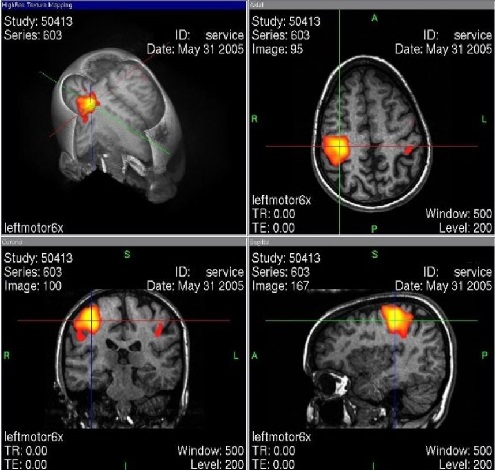

El Departamento de Radiología de Avila Rayos X contamos con un completo sistema de digitalización de imágenes diagnósticas, confiable para los estudios de radiología convencional, tomografía, resonancia y estudios especiales el cual permite que la lectura de los estudios sea más oportuna.